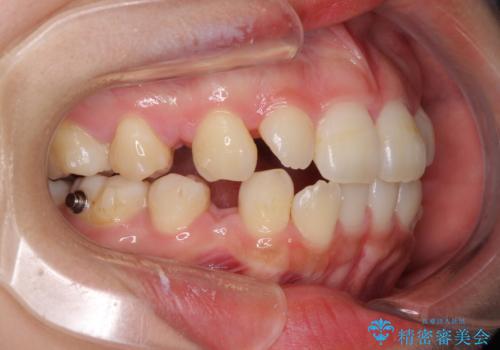

診断の結果、上顎左右第一小臼歯4本抜歯により、叢生を解消するとともに口元を引っ込めていくことが望ましいと判断しました。

抜歯矯正による口元の改善にはワイヤー矯正が望ましいのですが、ダンサーとしての仕事を行っているため、インビザラインにて治療を行うこととしました。

インビザラインによる矯正治療は、どれだけマウスピースを外す時間を短くできるかが成功の鍵となりますが、抜歯矯正ではよりシビアに要求されます。

こちらの患者様は、1日22時間以上を厳守してくださり、3年強で終えることができました。